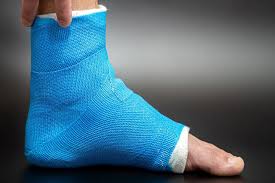

집에서 할 수 있는 초기 대응

피로 골절이 의심될 때 가장 중요한 것은 “참는 것”이 아니라 사용을 줄이는 것입니다. 통증을 유발하는 활동을 계속하면 뼈에 가해지는 부담이 더 커집니다.

• 달리기, 점프, 장시간 걷기 등 통증을 유발하는 활동 중단

• 하루 중 가능한 한 체중 부하 줄이기

• 통증 부위에 짧은 시간 냉찜질로 통증 완화

• 통증이 가라앉았다고 바로 활동량을 늘리지 않기

테이핑이나 보호대만으로 버티는 것은 일시적인 도움은 될 수 있지만, 근본적인 해결책은 아닙니다. 특히 통증이 반복된다면 반드시 휴식이 우선입니다.